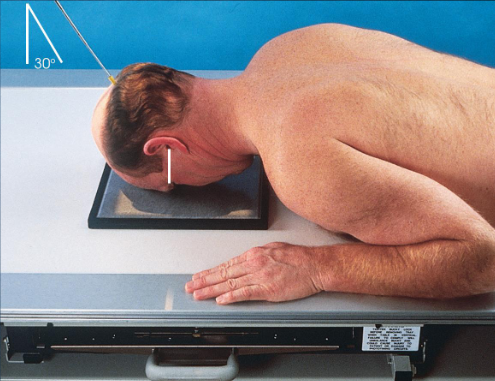

PA axial (exaggerated Caldwell) orbits

patient position:

upright or recumbent

part position:

rest forehead and nose on IR

IR centered ¾ inches distal to nasion

adjust head to place MSP and OML perpendicular to IR

respiration suspended

CR:

30 degrees caudad, through center of orbits

non-grid technique recommended to reduce magnification and eliminate possible artificats